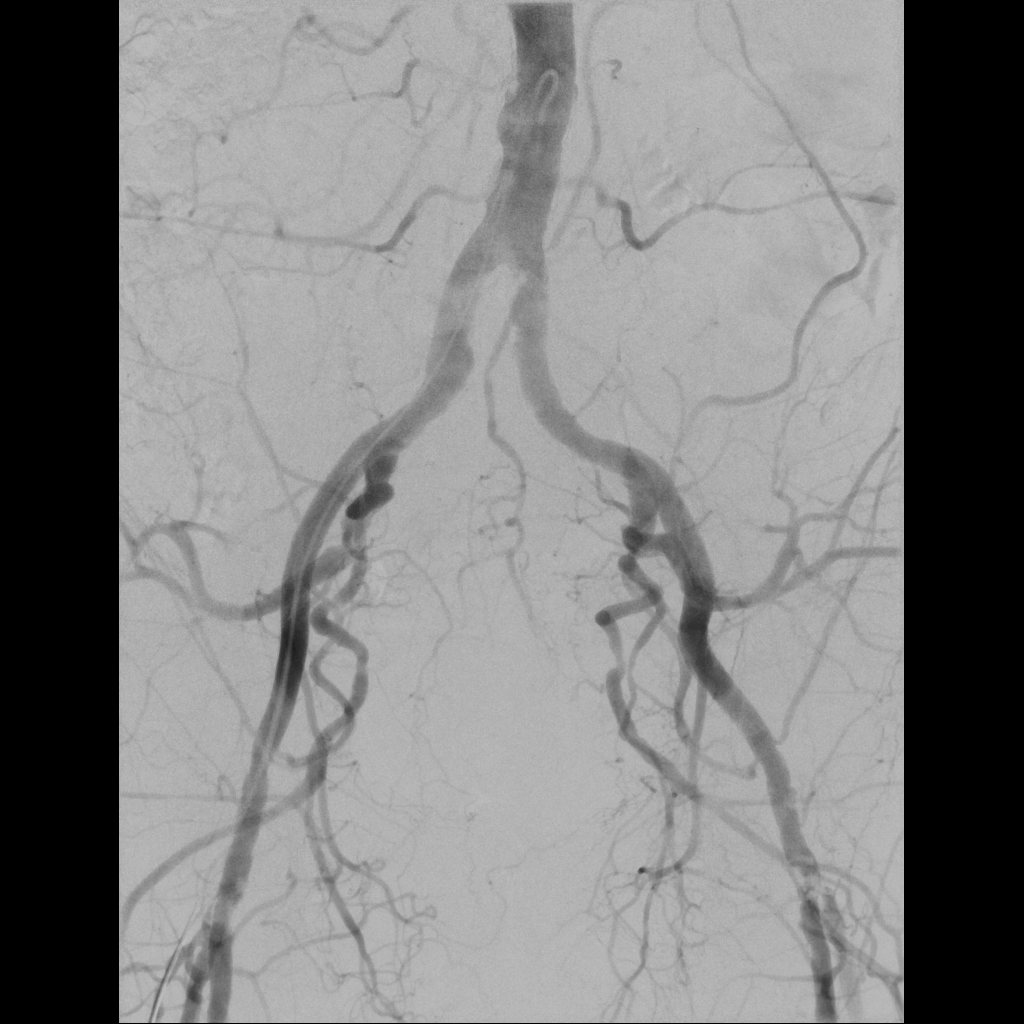

Inteventionelle Radiologie-Teil der Diagnostischen Radiologie oder ein eigenständiges Fachgebiet?

Die Entwicklung und Integration der interventionellen Radiologie im klinischen Alltag wird weltweit unterschiedlich gehandhabt. Während sie in den USA bereits als eigenständiges Fachgebiet anerkannt ist, gilt sie in Deutschland nach wie vor als fakultatives Teilgebiet innerhalb der Radiologie.

In der interventionellen Radiologie beschränkt sich die Tätigkeit des Radiologen nicht allein auf die bildgebende Diagnostik. Vielmehr übernimmt er eigenständig minimalinvasive Eingriffe und trägt dabei die Verantwortung für die prä-, peri- und postoperative Versorgung der Patient: innen.

Mit diesem Wahlfach möchten wir Ihnen praxisnahe Einblicke in das vielseitige und verantwortungsvolle ärztliche Arbeiten in der interventionellen Radiologie ermöglichen.